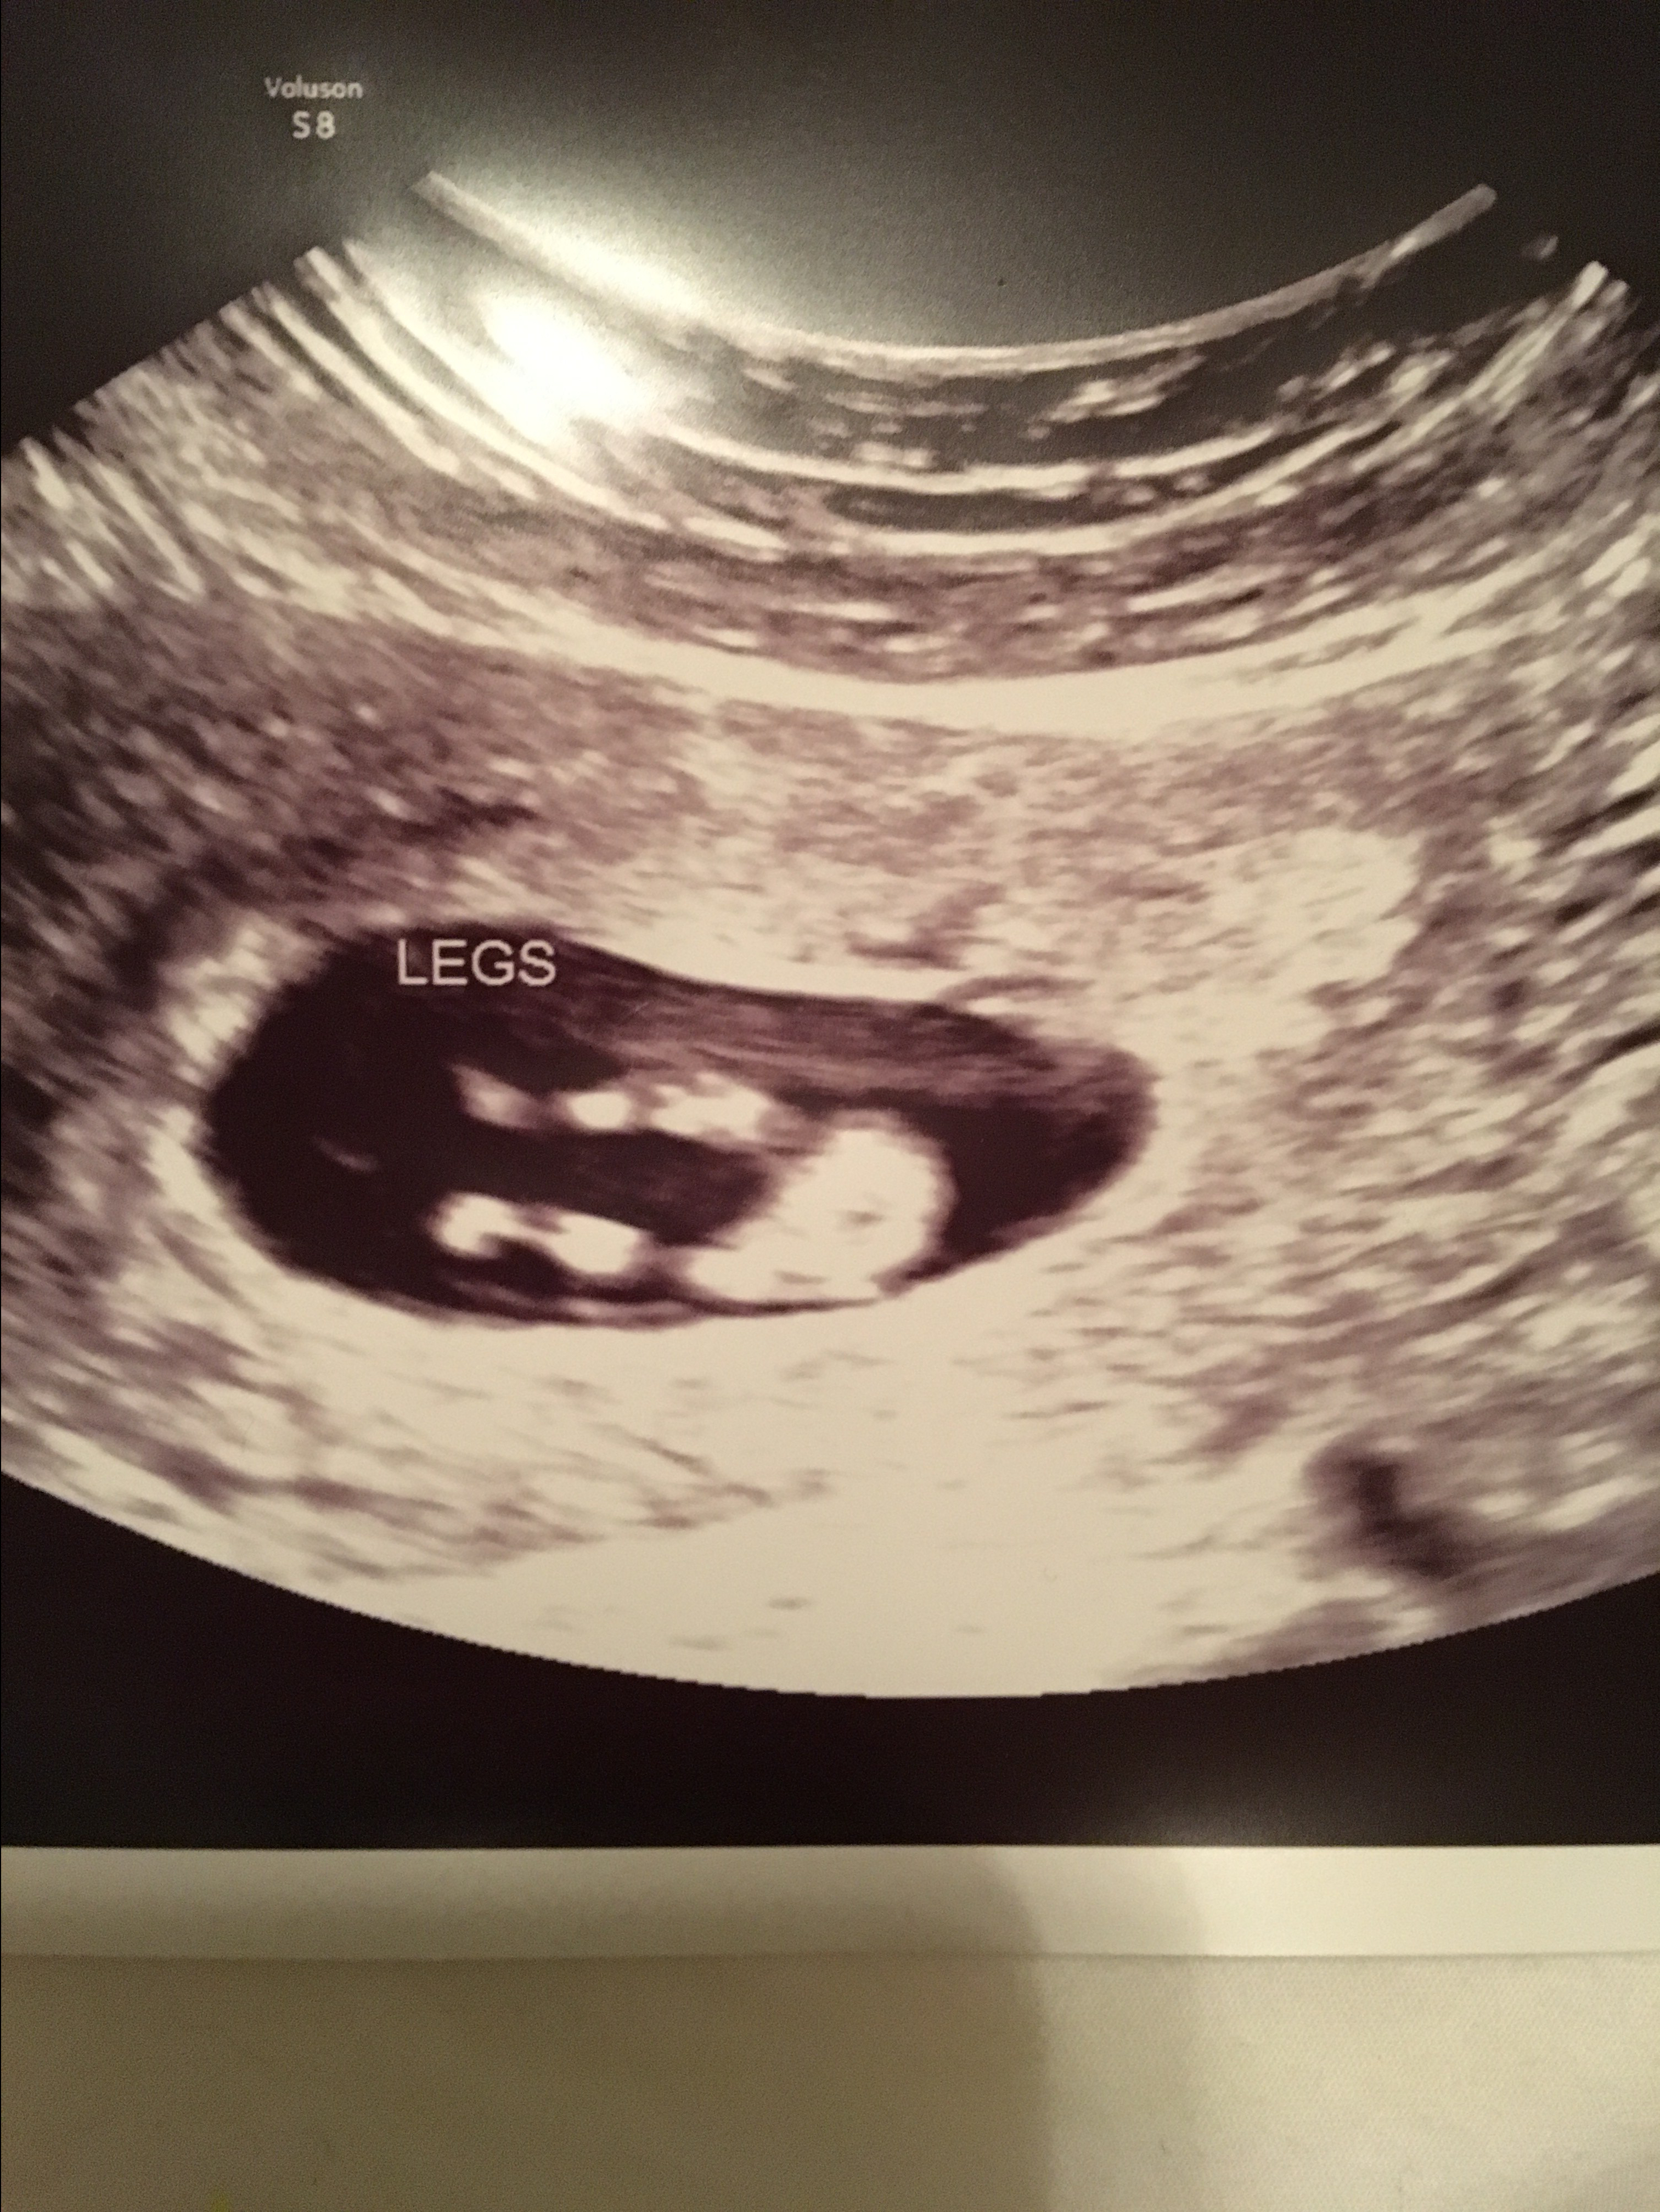

So, it’s been a little while, and in case you haven’t heard yet- Will and I are finally expecting a baby again! However, this time we have finally made it to 16+ weeks (WHICH IS SO EXCITING!) The picture above is from a little over 11 weeks- we’ll get some new glamour shots on Friday!

At our last appointment our baby did show us his/her behind….!

Personally, we think the baby kind of looks like an alien right now….